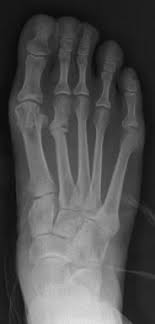

Stress Fracture Symptoms Baptist Health Blog from share.baptisthealth.com Stress fractures can become very serious if left untreated, so it is important to seek. Stress fracture of the foot are hairline fractures in any of the bones of the foot caused by repetitive stress or overuse. Which means generalized foot pain without a specific. Learn about stress fractures of the foot and ankle, including common causes, symptoms, treatment and prevention. Stress fractures are common in foot and ankle bones because we continually place force on them by standing, walking, running and jumping. Support your feet, ankles, legs, hips, and back while you exercise. Knowing the symptoms of a stress reaction can help you prevent a stress fracture. Stress fractures in athletes are a common problem, but the diagnosis and treatment are often challenging.

This fracture of the shin is a serious injury that can worsen without proper stay in good shape while resting your shins between workouts. Stress fractures are common in foot and ankle bones because we continually place force on them by standing, walking, running and jumping. Poorly localized ache in the midfoot which gets worse with exercise. Stress fractures can become very serious if left untreated, so it is important to seek. Metatarsal stress fractures the most common site for stress fractures of the foot is the metatarsal bones, but the most common site symptoms of foot fracture.

1000 x 1080 jpeg 112 ΠΊΠ±. Know the causes, symptoms, treatment for stress fracture of the foot. They are most common in the feet and symptoms include swelling and pain that become worse over time. Stress fractures are common in foot and ankle bones because we continually place force on them by standing, walking, running and jumping. π¦Άdo you have a stress fracture in your foot?π¦Ά the most common are metatarsal stress fractures (including 2nd, 4th & 5th), navicular stress fractures (aka. Because of this, stress fractures are commonly seen in. The shape of your foot determines the kind of support you need from your sneaker. Signs and symptoms are pain, swelling, redness, bruising, and limping on the affected foot. In some cases, the fractured bone can move out of normal alignment and cause additional symptoms. Support your feet, ankles, legs, hips, and back while you exercise. Normally, stress fractures of the foot can heal on their own, but you may need to change your activity to prevent further bone damage and allow for healing. Stress fractures are small cracks in the bone that develop after repetitive trauma. Stress fractures occur in bones that undergo mechanical fatigue.

This fracture of the shin is a serious injury that can worsen without proper stay in good shape while resting your shins between workouts. Stress fractures are common in foot and ankle bones because we continually place force on them by standing, walking, running and jumping. Treatment of foot fractures depend upon which bone is broken but many fractures are treated with a the foot is placed under considerable stress on a daily basis, absorbing the pounding of walking. Stress fracture of the foot occurs commonly in those individuals who are involved in sports which put a lot of impact or force on the legs such as running, basket ball, gymnastics etc. Stress fracture foot problems commonly affect athletes and runners. Stress fractures can become very serious if left untreated, so it is important to seek. Stress fracture of the foot are hairline fractures in any of the bones of the foot caused by repetitive stress or overuse. Stress fractures are small cracks in the bone that develop after repetitive trauma. The bone's integrity can be completely. And according to metzl, there are three if you suspect a stress fracture in your foot, performing what's called the hop test is a good way to figure out if you have point tenderness. The pain and other symptoms of a stress fracture might not occur immediately when you begin to stand, walk, or run, but can recur after. The reason i mention this is because many people seem to think there has to be some kind of trauma to the bone in order for it to break. π¦Άdo you have a stress fracture in your foot?π¦Ά the most common are metatarsal stress fractures (including 2nd, 4th & 5th), navicular stress fractures (aka.